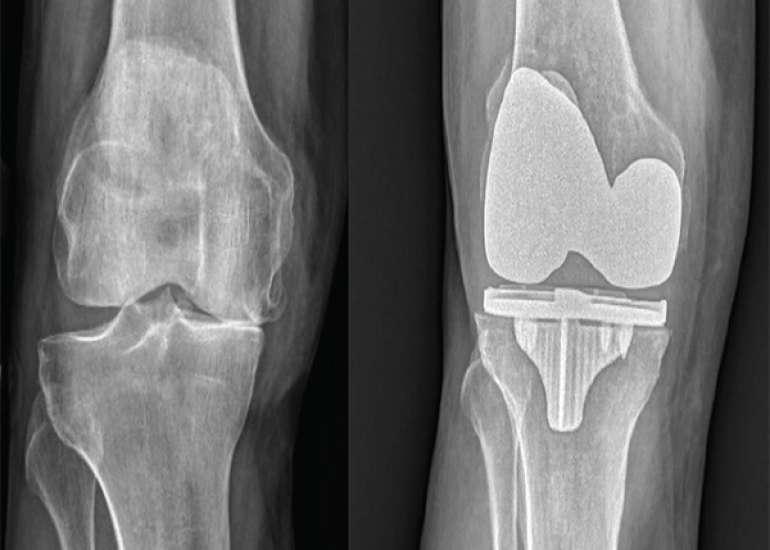

Director (Orthopaedics & Joint Replacement) & Head of Unit-1, Max Smart Super Speciality Hospital, Saket